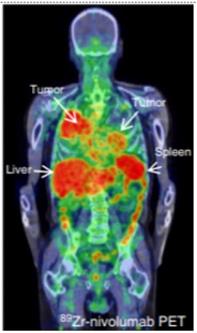

Figure 4

89Zr-labeled Nivolumab PET (37.09 MBq, 162 h p.i.) demonstrate heterogeneous tracer uptake within and between tumors. (Adapted for use under Creative Commons license http://creativecommons.org/licenses/by/4.0/ from Niemeijer, A.N., Leung, D., Huisman, M.C. et al. Whole body PD-1 and PD-L1 positron emission tomography in patients with non-small-cell lung cancer. Nat Commun 9, 4664 (2018). https://doi.org/10.1038/s41467-018-07131-y)

Adnectins, small protein molecules of ~10kDa size, have been developed against different targets as imaging agents. Adnectins are engineered based on the framework of the human 10th fibronectin type III domain (10FN3). They are structurally similar to variable domains of antibodies and are suitable as PET imaging agents owing to their small size, a non- or low-immunogenic profile, and pharmacokinetic properties [25]. Adnectins lack disulfide bonds and can be designed against a specific target with low nanomolar or even picomolar affinities. 18F-BMS-986192, an adnectin specific for PD-L1, was developed and used for imaging PD-L1 in lung cancer patients (Figure 3). The biodistribution showed uptake in marrow and spleen, sites of high PD-L1 expression, while uptake in lesions showed heterogeneity between patients as well as for different lesions in a patient. 89Zr-Nivolumab is radiolabeled an anti-PD-1 antibody that has shown ability to assess target expression in patients (Figure 4). Combined imaging with 89Zr-Nivolumab and 18F-BMS-986192 allowed for simultaneous assessment of both PD-1 and PD-L1, that demonstrated variation in uptake, thereby expression of PD-1 and PD-L1 across lesions in patients [26, 27]. Preclinical imaging in mice noted 3.5 times higher uptake in tumors expressing PD-L1 as compared to control animals. Specificity was further confirmed with blocking of radioligand binding in a dose-dependent manner [28].